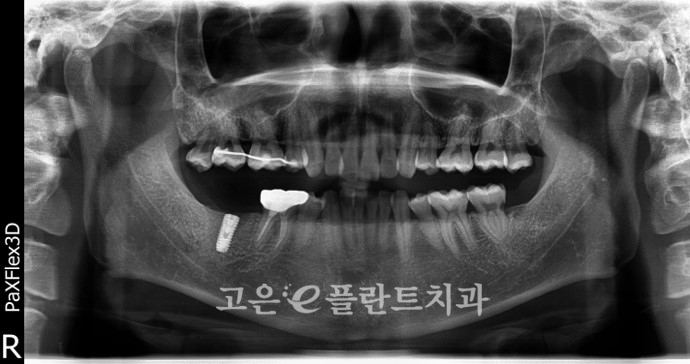

정기적으로 체크 하며 고정력을 확인한 뒤,

최종 보철물까지 진행한 사진입니다.

이처럼 신경치료를 진행한 후

크라운으로 씌워주지 않는다면

강한힘을 받는 어금니의 경우라면

쉽게 깨져나갈 수 있습니다.

그렇기에 꼭 ! 크라운으로

마무리 해주셔야 된다는 사실

잊지 마시길 바랍니다 :)